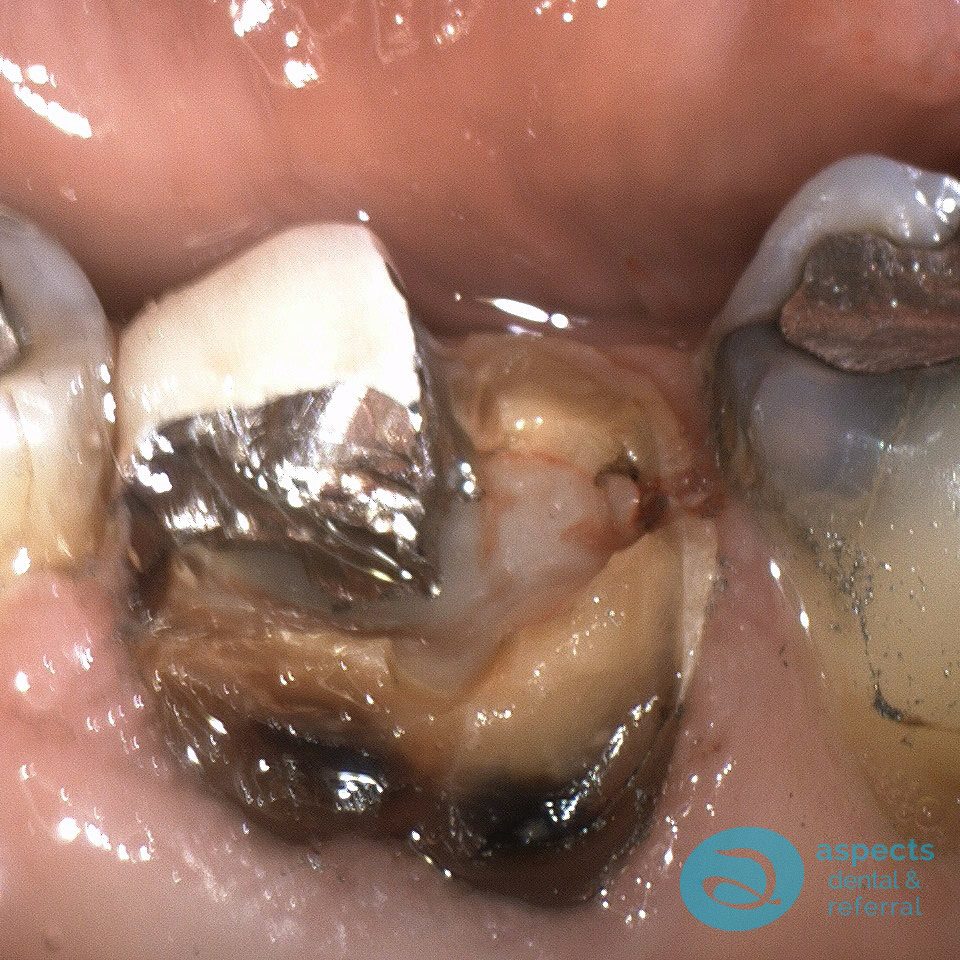

Our Dental Patient presented with a failing long-term Dental Crown and significant loss of tooth structure, rendering the tooth non-restorable. The tooth was subsequently extracted.

Failing Dental Crown & Tooth Loss